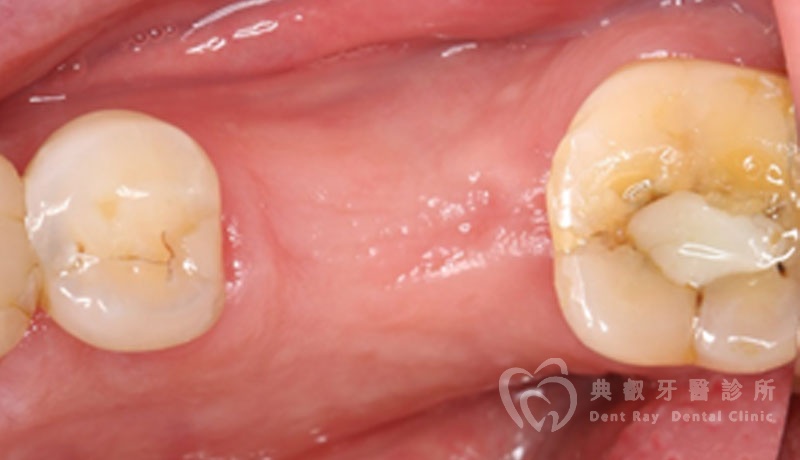

植牙案例一